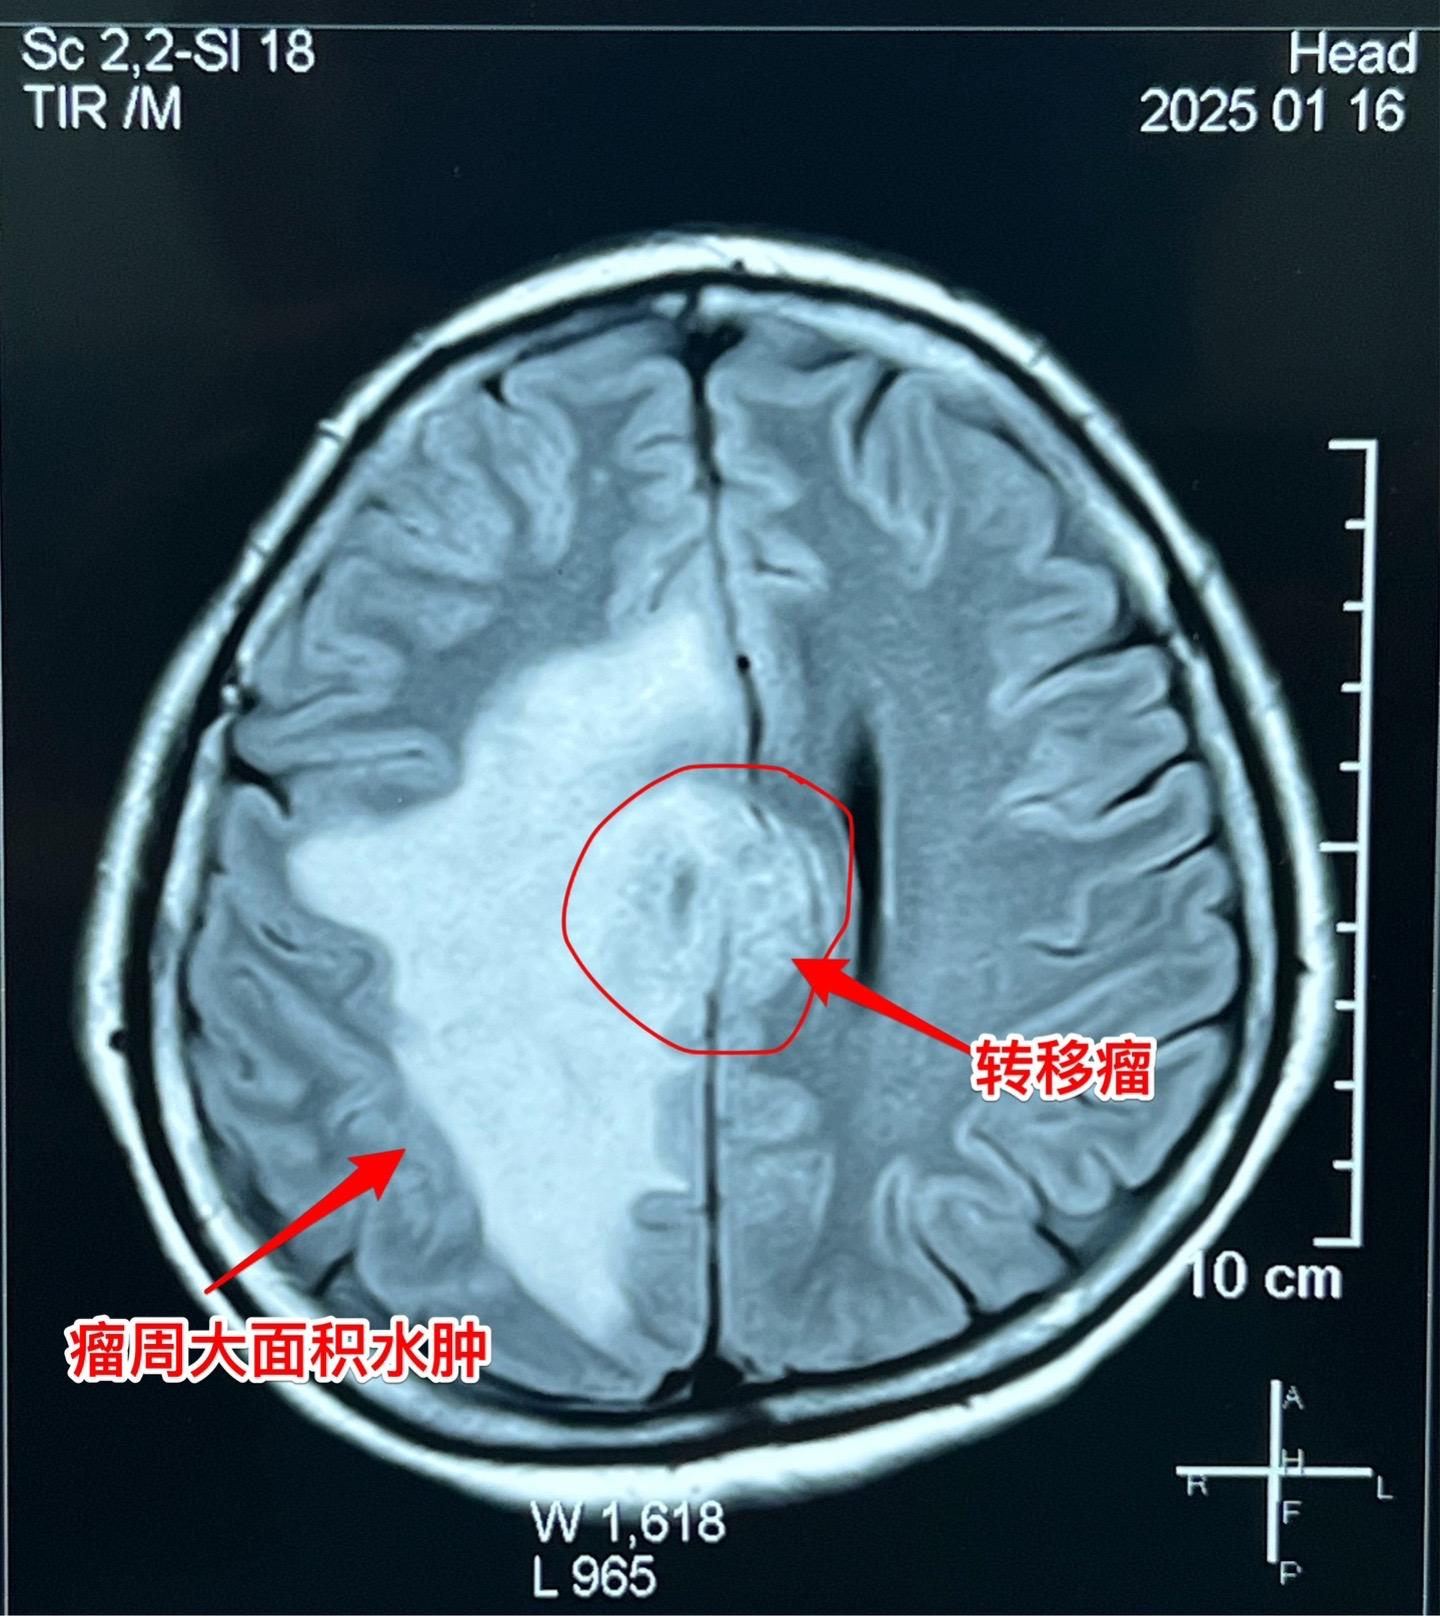

乳腺癌也能转移到脑部。脑部的转移瘤约80%来源于肺癌,绝大多数是腺癌。 乳腺癌发病率虽然低于肺癌,但也很常见。乳腺癌也可能转移到脑部。 这个54岁女性在7个月前先发现 脑部有个瘤,随后发现了乳腺癌,作了乳腺癌切除手术及内分泌治疗。多次复查磁共振显示脑部的瘤体积在增大,而且病人也出现头痛症状,故来作手术。 1月23日作了手术,顺利切除肿瘤。术前病人担忧出现偏瘫症状,手术后并没有出现。 针对这个病随后还需要综合治疗。